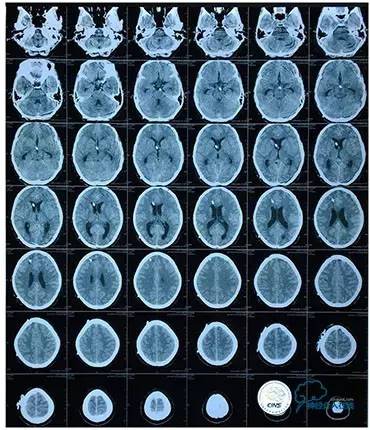

2016-5-19 MRI

病史:患者于1年余前,因头部外伤在外院行头颅CT提示:未见异常。约3月后患者出现头痛、发作性意识丧失,在当地医院行头颅CT及MRI提示:未见明显异常。诊断为外伤性癫痫,予以对症治疗,未见明显好转。6月余前,无明显诱因出现鼻腔漏液,予以保守治疗,此后鼻腔间断漏液,漏液后头痛缓解。13天前因高热、恶心、呕吐在外院诊断为颅内感染(肺炎链球菌),予以抗炎等对症治疗2周后鼻漏停止,体温正常,CSF常规、生化正常,但头痛仍未缓解,转入我院神经内科治疗。反复腰穿颅内压450-500mmH2O左右,脑脊液常规及生化均正常。颅脑CT及MRI、MRV提示:左侧顶叶硬膜下血肿,鼻窦炎、乳突炎、左侧横窦、乙状窦闭塞、右侧横窦、乙状窦狭窄。予以华法林抗凝治疗2周,维持INR2-3,患者头痛仍无明显缓解,颅内压无下降,转入我科。

病史:患者于1年余前,因人流术后出现发作性四肢抽搐伴口吐白沫,头痛及双眼视力下降在外院行颅脑MRI及MRV提示:右侧横窦、乙状窦狭窄,予以低分子肝素抗凝治疗2周,颅内压无明显下降,视力下降严重,遂行脑室腹腔分流术,术后患者头痛缓解、双眼视力稍有改善。2周前患者再次出现头痛、发作性四肢抽搐及视力下降,在外院眼科予以治疗2周,头痛无明显改善,视力再次逐渐下降,遂转入我科。